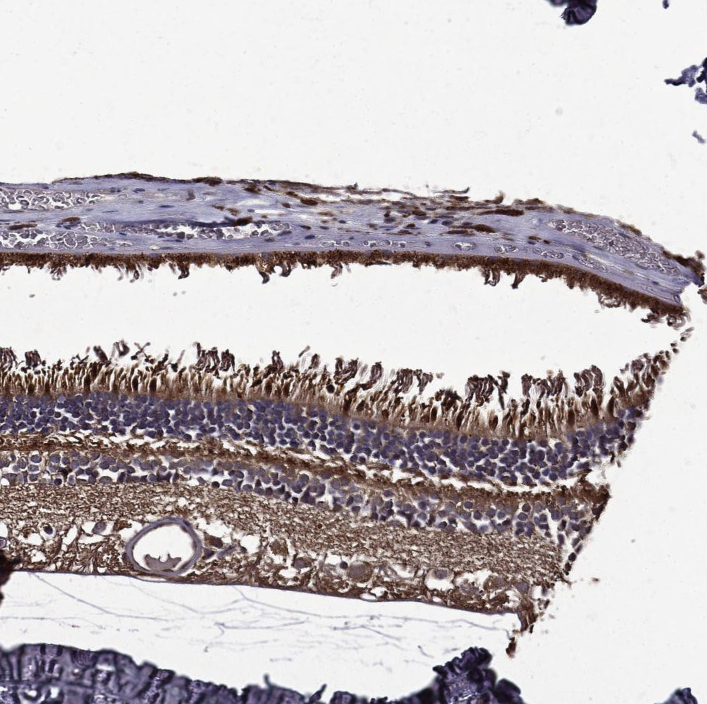

Immunohistochemical staining of human eye, retina shows strong cytoplasmic positivity.